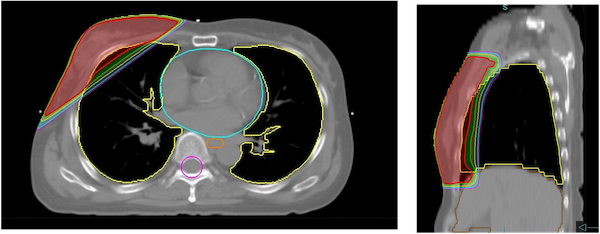

Radixactはトモセラピー技術をベースに進化させた放射線治療装置です。この装置は、高精度なIMRT(強度変調放射線治療)を広範囲かつ効率的に行うために設計されています。従来の治療装置では困難であった、複雑な形状や広範な病巣に対しても、極めて均一で精度の高い治療が可能になりました。

Radixactは、治療台(カウチ)がゆっくりと移動する間に、放射線発生装置が患者さんの周囲を360度回転しながら、らせん状(ヘリカル)に連続して放射線を照射します。従来の多方向からの照射に加え、全方向からのアプローチが可能になることで、腫瘍に線量を集中させ、周囲の正常臓器への線量(被ばく)を効果的に低減させることができます。

他のリニアック(放射線治療装置)と比べ、Radixactは広い照射範囲を一度にカバーできるという利点があります。脊髄全体や広い範囲にわたるリンパ節への照射など、治療範囲が広い場合でも、途切れなく高い精度で治療できます。また、複数の病変が体内の広範囲に散らばっている場合でも、効率的に、かつ同時に高精度な治療計画を立てて実行できる可能性があります。

従来、左鎖骨窩のリンパ節と左胸壁に分けて行っていた治療を、つなぎ目なく一度に治療することができるようになりました。